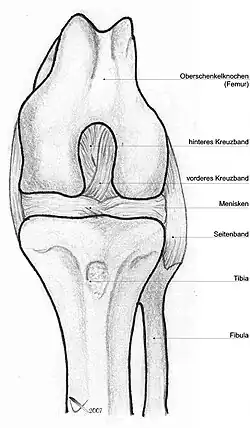

Die Kreuzbänder (Ligamenta cruciata) ziehen von der Grube zwischen den Oberschenkelknorren zum Schienbein. Von der Seite und von vorn betrachtet überkreuzen sie sich dabei in ihrem Verlauf.

Indem die Kreuzbänder ein verschobenes Abgleiten der Gelenkflächen nach vorn oder hinten (Translation) verhindern, stabilisieren sie das Knie. Zusätzlich hemmen sie die Drehbewegung, vor allem die Einwärtsdrehung, bei der sie sich umeinander wickeln und das vordere Kreuzband sich spannt. Bei der Auswärtsdrehung wickeln sie sich auseinander, wodurch das Knie bei maximaler Streckung immer ein wenig nach außen gedreht wird (Schlussrotation). Die klassische Verletzung des vorderen Kreuzbandes tritt daher, z. B. beim Skifahren, bei gebeugtem Knie und Einwärtsdrehung unter Gewalteinwirkung auf.

Vorderes Kreuzband

Das vordere Kreuzband (Ligamentum cruciatum anterius – bei Tieren Ligamentum cruciatum craniale) zieht von der vorderen Einmuldung zwischen den Schienbeinknorren zur Seite und etwas nach hinten, um an der Innenseite des seitlichen Oberschenkelknochens anzusetzen. Dabei teilt es sich in ein vorne-mittiges und in ein hinten-seitliches Bündel auf. Durch die weite Fächerung der Ursprungsfläche dieser Bündel ist sowohl bei Beugung, als auch bei Streckung ein Teil des vorderen Kreuzbandes gespannt. Dadurch verhindert es bei ausgestrecktem Bein eine Überstreckung (Hyperextension), während es bei Beugung dem Vorschub des Schienbeines entgegenwirkt („vordere Schublade“).

Hinteres Kreuzband

Das hintere Kreuzband (Ligamentum cruciatum posterius – bei Tieren Ligamentum cruciatum caudale) ist kräftiger und hat seinen Ursprung in der hinteren Einmuldung des Schienbeinplateaus und zieht nach vorne-mittig, um an der seitlichen Vorderfläche des inneren Oberschenkelknochens anzusetzen. Es spannt sich bei Beugung und verhindert damit ein nach hinten gerichtetes Weggleiten des Schienbeines (hintere Schublade). Bei ausgestrecktem Bein unterstützt das hintere Kreuzband das vordere beim Vorbeugen einer Überstreckung. Seine Hauptaufgabe ist jedoch die Stabilisierung des Knies bei Beugung und unter Last.

Menisken

Da die miteinander in Verbindung stehenden (artikulierenden) Gelenkflächen nicht genau aufeinander passen, wird diese „Ungleichheit“ (Inkongruenz) durch halbmondförmige Faserknorpelscheiben, die Menisken ausgeglichen, die den Drehbewegungen folgen können. Eine weitere Aufgabe der Menisken besteht in der Vergrößerung der Kontaktfläche zwischen Schienbein und Oberschenkelknochen.

Man unterscheidet einen Innenmeniskus (Meniscus medialis), der C-förmig, größer und etwas unbeweglicher (da mit dem Innenband verwachsen) ist, und einen Außenmeniskus (Meniscus lateralis), der kreisförmig, kleiner und beweglicher ist (da er mit keinem Seitenband verwachsen ist). Die Menisken sind im Querschnitt keilförmig. Die hohe Kante liegt außen, die niedrige innen. Da die Oberschenkelknochen genau in der Mitte direkt auf dem Schienbeinplateau und peripher auf den Menisken aufliegen, tragen diese einen wesentlichen Teil der Last.

Seitliche Bandsicherung

Das Knie hat zwei Seitenbänder: ein inneres (Ligamentum collaterale tibiale) und ein äußeres (Ligamentum collaterale fibulare). In Streckstellung sind beide Seitenbänder (auch Kollateralbänder genannt) gespannt und verhindern somit die Drehbewegung, in Beugestellung verkleinert sich der Krümmungsradius, Ursprung und Ansatz nähern sich einander an und die Bänder sind infolgedessen entspannt. Beide Seitenbänder stabilisieren das Kniegelenk in seitlicher Richtung (Frontalebene), damit ein Wegknicken in eine O-Bein-Stellung (Genu varum) oder X-Bein-Stellung (Genu valgum) verhindert wird.